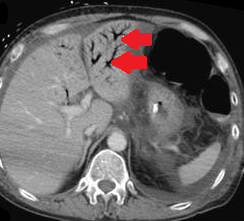

Παρουσία αέρα στο πυλαίο φλεβικό σύστημα, δευτεροπαθώς σε ισχαιμική κολίτιδα (Ευγενική παραχώρηση Dr. V. Penopoulos)